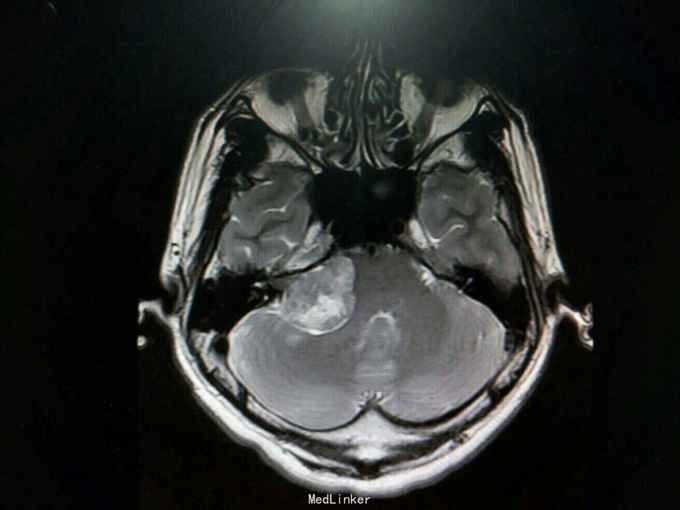

查体:生命体征平稳。神经系统检查提示:Ⅴ颅神经:右侧面部感觉稍减退,张口下颌无偏歪 。Ⅷ颅神经:右侧听力较左侧减退,无眩晕 。外院检查示行磁共振检查提示:右侧桥脑小脑角占位:听神经鞘瘤?辅助检查:颅脑MRI检查提示:右侧桥小脑角处可见类圆形占位性病变,边界清,形态规则,大小约24.8mm×33.8mm。右侧桥小脑角区占位,考虑听神经鞘瘤。

诊断:听神经鞘瘤 处理:右侧枕下乙状窦后入路听神经瘤切除术